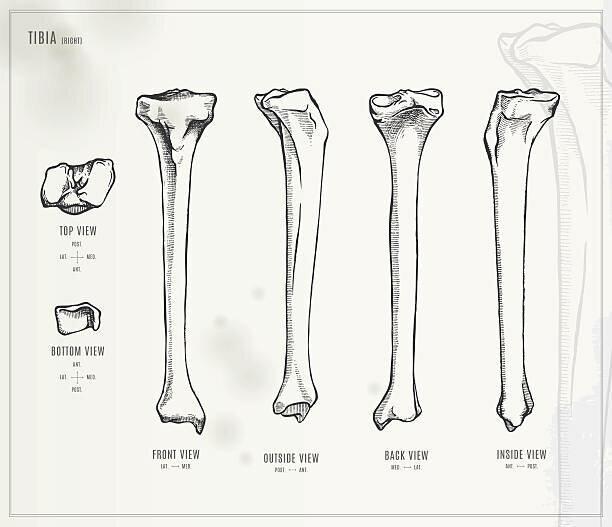

Хорошая картинка с изображением большеберцовой кости со всех сторон, в т.ч. сверху и снизу. Из интернета.